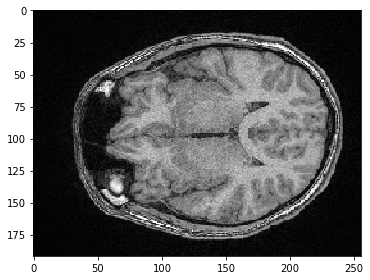

Nous pouvons également sélectionner un plan où tous les pixels ont la même position Y. Nous devons juste spécifier que nous souhaitons conserver tous les pixels en Z en utilisant la syntaxe :.

slice_image = image[:, 100]

imshow(slice_image)

../_images/ad292cbffaab643c3d9273781ac2d7a8cb9aeed56d351d1c201b74c79fcbef31.png